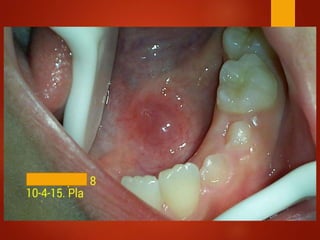

El documento es un registro médico odontológico que muestra las fechas de las visitas de un paciente al centro de salud El Raval, incluyendo exámenes y tratamientos realizados como la extracción de cálculos salivales en abril y mayo de 2012.